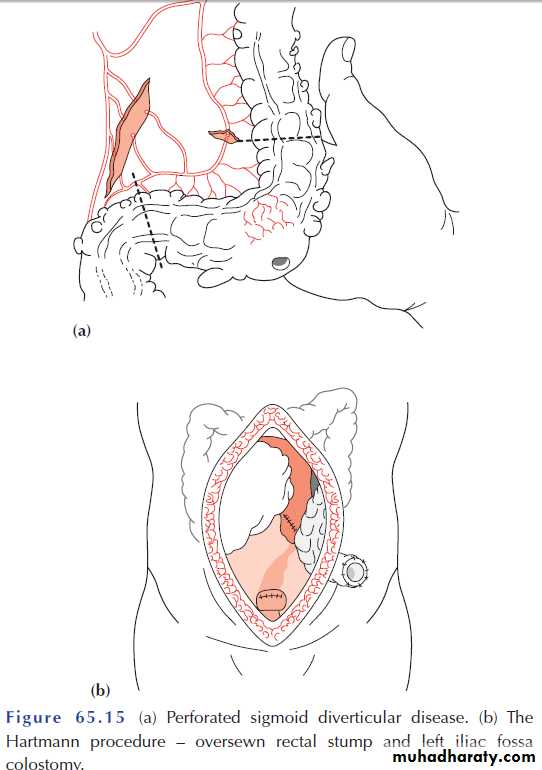

Operative procedures for diverticular disease